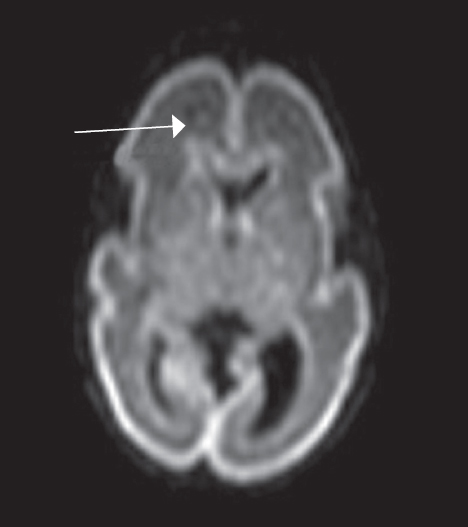

Patterns of neuroplasticity and cerebral maturation in preterm neonate can be assessed by MRI and cranial ultrasound. The score system of brain maturation includes the account of germinal matrix (GM) regression by MRI. The GM regression can be considered as pattern of neuroplasticity. There have been investigated the changes of neuroplasticity pattern or GM regression in preterm neonates with extremely low birth weight (ELBW) without intragerminal/intraventricular hemorrhages (n = 21). It is believe that the main causes of impair of GM are the intragerminal hemorrhages and hypoxia. The methods of study were cranial ultrasound (CU) and MRI. The measurement of GM was carried out by CU in anterior horn of the lateral ventricles of neonates in the study group (25-29 weeks). It was detected the GM regression in preterm neonates with increasing age, and complete GM regression to 30 week. MRI has been performed in 15 neonates from the study group on 27-38 weeks age with using the common pulse sequences – T1 WI, T2 WI and Flair. GM was detected by MRI up to 34 weeks inclusive by using the additional pulse sequence – DWI. By using common pulse sequences the GM was visualized up to 32 weeks age. Furthermore there has been pathological examination of GM in anterior horn of lateral ventricle in dead neonates from the study group (n = 3). We revealed the thickness reduction of GM in the lateral ventricles with increasing age of the dead neonates. Also we identified the delay of the GM reduction in two dead neonates 36-38 weeks age (post conceptual age) what may indicate the disorder of neuroplasticity in those preterm neonates. The performed study showed the capability of CU and MRI in examination of neuroplasticity in preterm neonates.